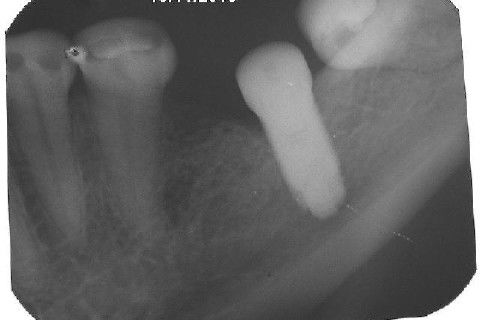

Iniciei esta etapa com o uso de um bisturi circular para contra ângulo. Na verdade, estou postando novamente este procedimento, mas realmente, cheguei depois a conclusão que não deveria ter agido assim nos dentes anteriores, onde a estética é primordial, não devemos remover tecido mole, mas manipular para promover um aumento de papila. Este bisturi é útil para dentes posteriores, adianta bastante o trabalho, é rápido, remove uma porção do formato e dimensão da plataforma do implante, a conta para adaptação do cicatrizador.